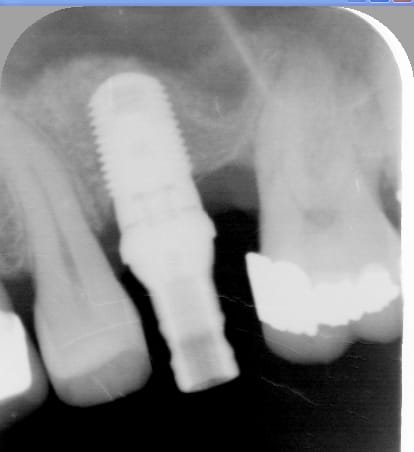

Le cas date de 2010, le sinus est traité par élévation crestale + mise en place de 2 mb de PRF dans le "trou" avant de combler au RTR et en dernier os récupéré du forage pour espérer qu'il reste contre l'implant.

J'ai pas pu enlever le prénom mais vous avez les dates dans l'ordre

La radio postée hier est un "contrôle à 6 ans avant d'implanter en 14

Honnêtement ta radio est pas terrible. T'as mis du biomat ?

Et bien moi je trouve ça joli.

Evidemment il y a du biomat, une bonne quantité. Plus de la moitié de l'implant est dedans.